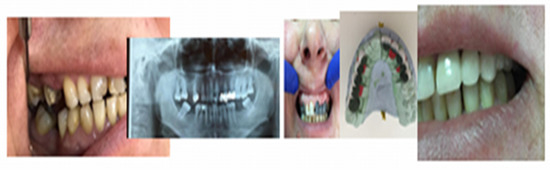

All kinds of specialized research on types of biomaterials used for endodontic restorations consider in the end the benefit of the patients, ensuring good biocompatibility, integration, stability, and functionality so that the predictable prosthetic rehabilitation increases quality of life by a proportion of 95% for the patients. Unidental restoration and Richmond crown result in an increase of 45%, and double prosthetic pieces elements result in an increase of 32% in a multiple construction bridge. A special importance can be observed in the approach of patients who presented clinical signs of dysfunctional syndrome in 25% who experienced pain, 15% with clinical signs of joint cracks and crepitation, and muscle dysfunctions in 35%, all due to occlusal imbalances, which require treatment with mouth guards and balneal–physical–kinetic therapy rehabilitation complex treatment in order to accomplish the principles of homeostasis and its stability [18,19,20] (Figure 13).

Figure 13. Images of the initial clinical situation, paraclinical orthopantomography examination, and the occlusal rehabilitation for the necessary foundation of the stomatognathic system homeostasis.